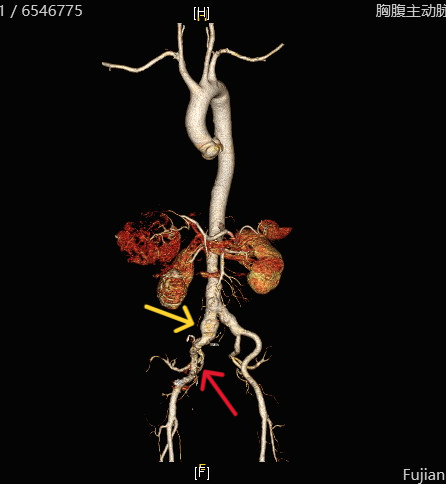

更让人揪心的是,陈老师还被检查出腹主动脉——右髂总动脉有一个范围达5.0×4.5cm的动脉瘤,并且动脉瘤周围已有破裂迹象

图示右髂总动脉瘤(黄色箭头)及可疑破裂处(红色箭头)

肝胆胰外科周松强主任医师介绍说,大动脉瘤体积越大,破裂风险越高,像陈老师这种囊状动脉瘤,破裂风险更为显著。一旦动脉瘤突发破裂,抢救成功率不超过10%。这三处隐患同时出现在陈老师身上,让他的病情变得异常复杂,每一处都足以致命,治疗难度可想而知。